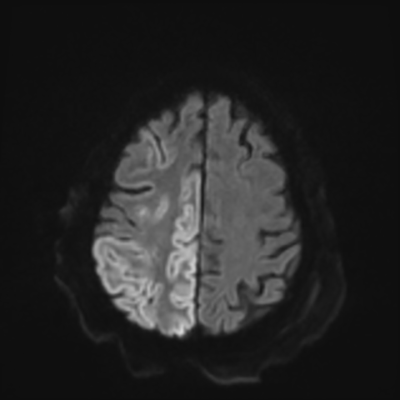

You come back the next day and see how things are going. The patient's electrographic record has shown a moderate encephalopathy (diffuse slowing, disorganization) with frequent right posterior quadrant delta slowing. Based on this result, and an adequately improved clinical examination, you give the okay to proceed with obtaining an MRI of his brain. This is shown below.

MRI brain (DWI)